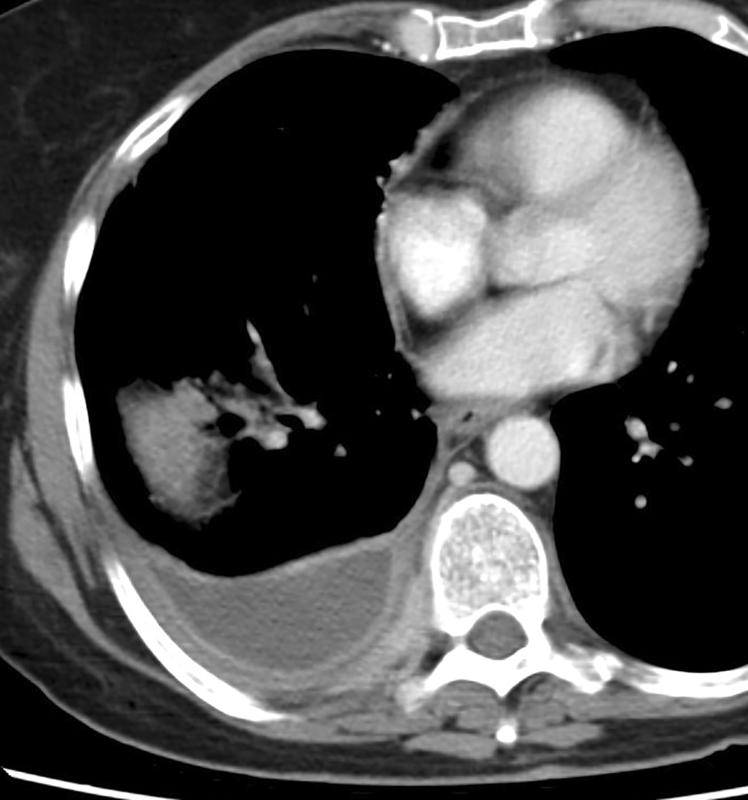

"split pleura"

split pleura 2